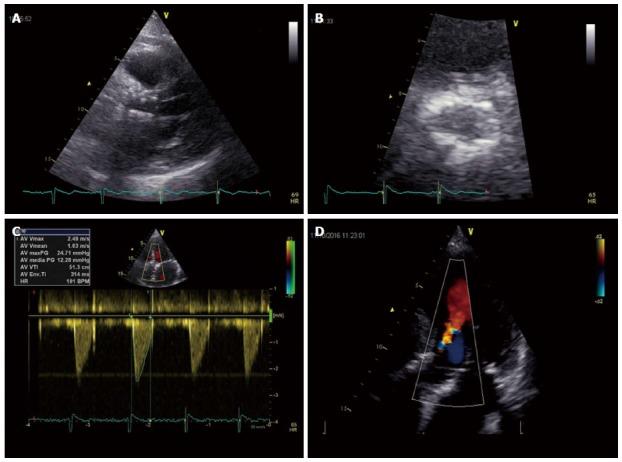

Transcatheter aortic valve replacement (TAVR) has been validated as a new therapy for patients affected by severe symptomatic aortic stenosis who are not eligible for surgical intervention because of major contraindication or high operative risk. Patient selection for TAVR should be based not only on accurate assessment of aortic stenosis morphology, but also on several clinical and functional data. Multi-Imaging modalities should be preferred for assessing the anatomy and the dimensions of the aortic valve and annulus before TAVR. Ultrasounds represent the first line tool in evaluation of this patients giving detailed anatomic description of aortic valve complex and allowing estimating with enough reliability the hemodynamic entity of valvular stenosis. Angiography should be used to assess coronary involvement and plan a revascularization strategy before the implant. Multislice computed tomography play a central role as it can give anatomical details in order to choice the best fitting prosthesis, evaluate the morphology of the access path and detect other relevant comorbidities. Cardiovascular magnetic resonance and positron emission tomography are emergent modality helpful in aortic stenosis evaluation. The aim of this review is to give an overview on TAVR clinical and technical aspects essential for adequate selection.

经导管主动脉瓣置换术(TAVR)已被确认为一种针对严重症状性主动脉瓣狭窄患者的新疗法,这些患者因主要禁忌症或高手术风险而不符合手术干预条件。TAVR的患者选择不仅应基于对主动脉瓣狭窄形态的准确评估,还应基于多项临床和功能数据。在TAVR之前,应优先使用多种成像方式来评估主动脉瓣和瓣环的解剖结构及尺寸。超声是评估此类患者的一线工具,可对主动脉瓣复合体进行详细的解剖描述,并能足够可靠地估计瓣膜狭窄的血流动力学情况。血管造影应在植入前用于评估冠状动脉受累情况并制定血运重建策略。多层计算机断层扫描起着核心作用,因为它可以提供解剖细节,以便选择最合适的假体,评估入路路径的形态并检测其他相关合并症。心血管磁共振和正电子发射断层扫描是有助于评估主动脉瓣狭窄的新兴检查方法。本综述的目的是概述TAVR在充分选择患者时所必需的临床和技术方面。